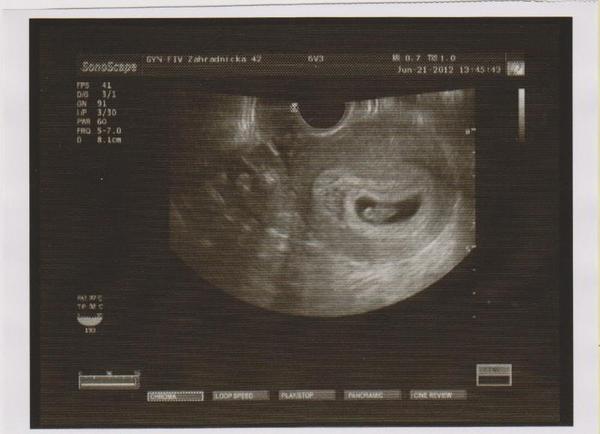

Hlasim sa z 1. UTZ - jeden živý mrňúsek. 😵 😵 😵 Vsetko je v poriadku ... uz mam zacat vysadzovat utrogestan. Dostala som prepustaciu spravu uz pre mojho gyndosa.

Dakujem, kocky ... straaasne sa tesim. Aj mi dali fotku - uz som sa do neho (nej) šílene zamilovala - furt na neho (nu) kukam 😀 😀 ... vecer ju sem skusim naskenovat, ak to pojde.